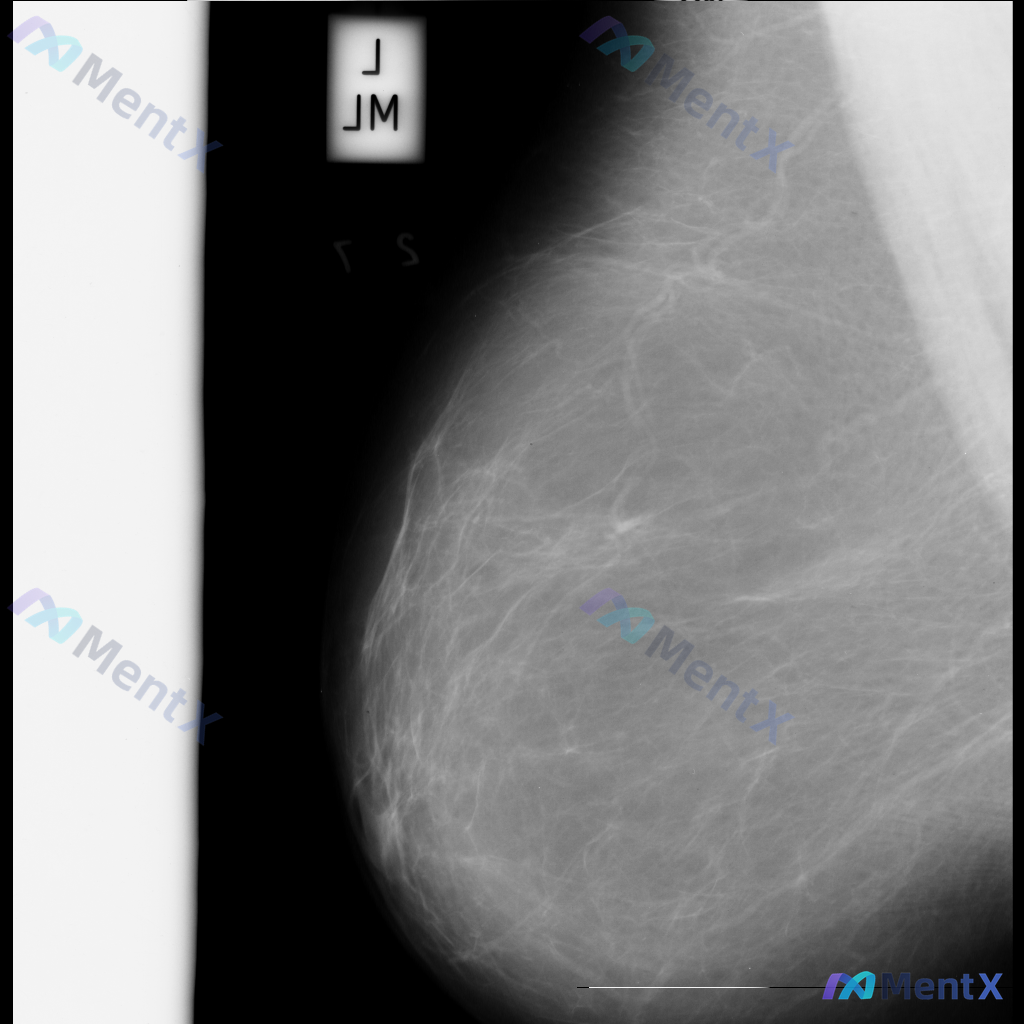

整理了一张乳腺钼靶影像的讨论资料,先和大家分享一下读片描述: 影像可见:不规则、高密度肿块/不对称致密影,伴有毛刺状边缘、结构扭曲和散在钙化。 目前考虑可能存在几种不同的异常方向,想先听听大家的第一反应——单看这组影像特征,你会先往哪种情况考虑? 也可以说说你最关注的是哪一点表现。